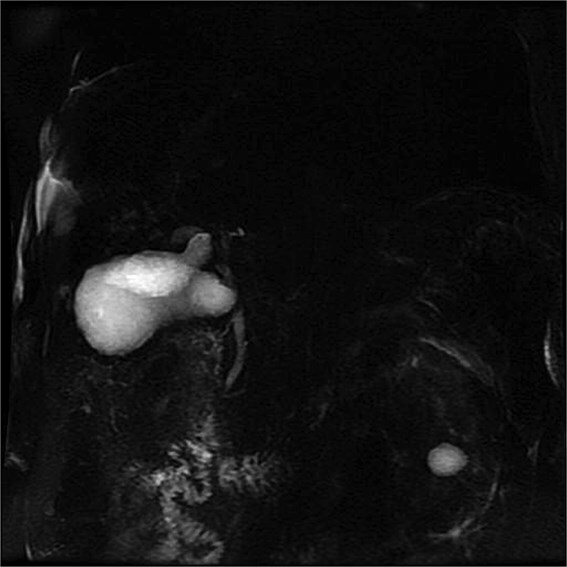

Gallbladder duplication is a rare congenital anomaly. Abnormal biliary anatomy is associated with an increased risk of complications, such as bile duct injury, during cholecystectomy. In this article, we present a clinical case of gallbladder duplication identified preoperatively by magnetic resonance cholangiopancreatography, which guided surgical planning. A 70-year-old man was admitted with acute cholecystitis, low-grade fever, jaundice, and dyspnea. Magnetic resonance cholangiopancreatography revealed a duplicated gallbladder (Type H). During surgery, the chronically inflamed upper gallbladder was completely resected. The larger lower gallbladder, with acute cholecystitis and a Mirizzi-like pattern, was partially resected due to severe inflammation and the inability to identify the cystic duct. The patient had an uneventful course. Gallbladder duplication is a rare congenital anomaly that may be associated with other congenital anomalies. Thorough preoperative imaging studies, meticulous surgical technique, and rigorous intraoperative monitoring are essential, as these abnormalities can lead to serious injuries.

Abstract Image